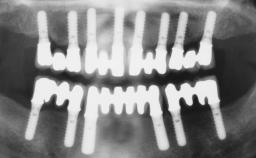

Immediate Loading of Six Implants in the Mandible and Six Implants in the Maxilla and Final Restoration with Full-Arch CAD/CAM Metal Framework FDPs Involving Digital Planning and Guided Surgery

# of Implants 12

Modality 6+ implants with immediate loading

Retention Screw-retained, with 4 or more splinted implants Screw-retained, with 4 or more splinted implants